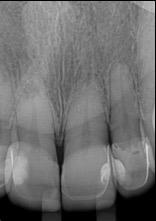

Dientes 31 y 41 - Reabsorción Interna / Conducto obturado con BIO-C® REPAIR. Imágenes cedidas por la Dra. Cimara Barroso.